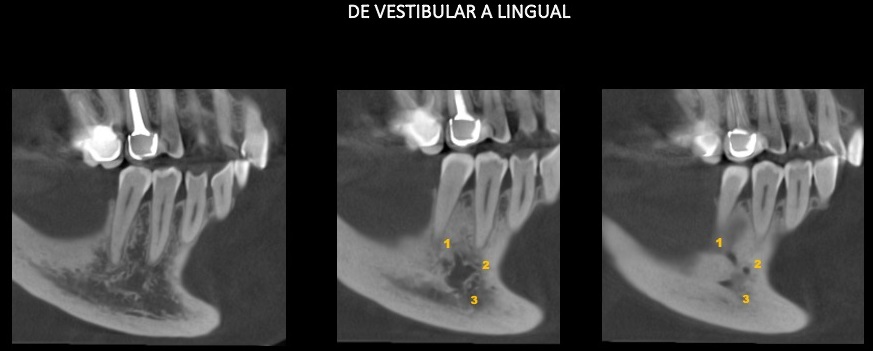

Paciente femenino de 53 años acude para una evaluación general. A la evaluación de la tomografía volumétrica (cone beam) bimaxilar en los cortes axiales (Figura 1) y tangenciales (Figura 2) se observa que adicional al foramen entoneano de lado derecho la presencia de dos forámenes accesorios de menor calibre uno mas hacia medial y el otro hacia caudal.

CORTES TANGENCIALES